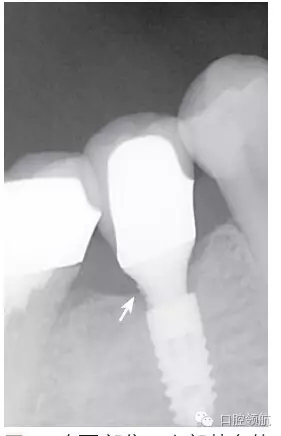

種植體的基臺與上部修復體的密合性,通過口腔X線片進行檢查,確認種植體周圍有殘留的粘接劑(圖2),使用探針等器械盡力清除剩余粘接劑,避免預后不良因素的產(chǎn)生。然后,通過X線片從投照的方向檢查確認剩余的粘接劑,完全沒有殘留粘接劑的實際狀態(tài)(圖3)。

圖2 在(左下第五顆牙)部位,上部基臺的遠中鄰面區(qū)域,看到了殘留的剩余粘接劑。